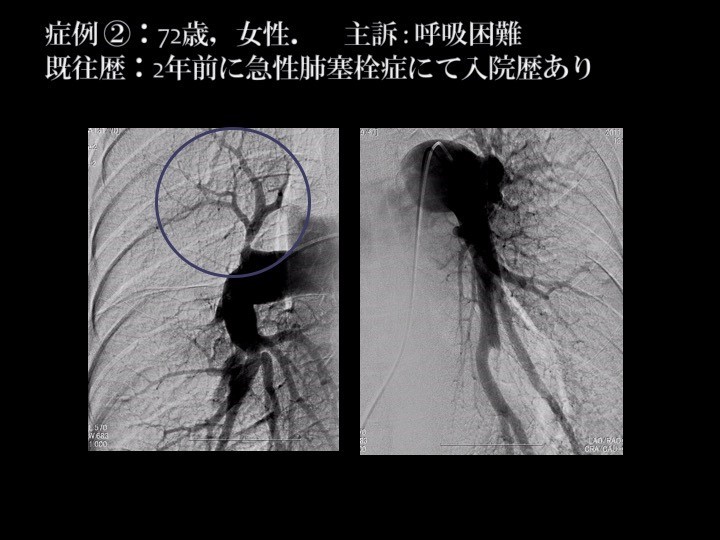

これは当院における72歳の女性の症例です。この画像でも〇囲み部分のように血管が詰まっているところがいくつか確認できます。血流が妨げられて画像上で薄くなっている部分を血管内視鏡というカメラで見たところが下の画像です。

血栓は通常、赤く見えますが、このように壁にへばりついて器質化した血栓は白っぽく写っています。器質化した血栓はヘパリンや血栓溶解剤を使っても溶けません。ところがこの部分をバルーンで拡張してみると、へばりついていた血栓が剥がれ、血管に新しい枝ができて再生していきます。

この患者さんの場合、ところどころに点在する塞栓部に対してBPAを施行した結果、110mmHgほどあった圧力が46mmHgに下がり、肺動脈拡張薬を併用することで最終的に27mmHgにまで下げることができました。煙突の煤(すす)のように付いていた器質化した血栓を、あたかも煤払いをするように全部拡げていくことで圧が正常化し、727.6もあったBNPの値が31.9になりました。この方は今もお元気で普通に生活していらっしゃいます。